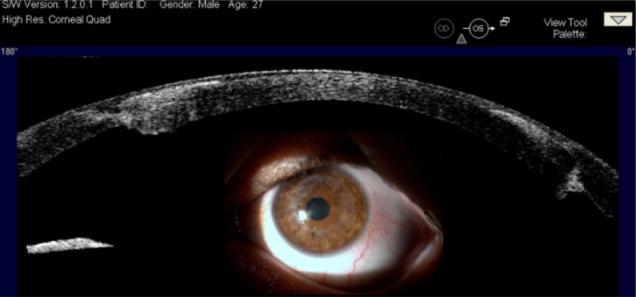

Seventy eyes of 58 patients who had penetrating keratoplasty were included in the study. High resolution AS-OCT scans of the cornea and the anterior segment were performed before and after transplantation in 17 eyes with the Visante™ optical coherence tomography. Fifty-three eyes were examined in the late postoperative period.

The mean follow-up was 4.3 years (range, 1-15 years). Six different graft-host junctions were identified. Three patients with graft rejection, four patients with anterior synechia, and three patients with corneal ulcer were evaluated. Preoperative evaluation of eyes with semiopaque and totally opaque corneas revealed important information about anterior segment structures additional to slit-lamp findings.

AS-OCT is a useful complementary tool for the evaluation of penetrating corneal transplantation surgery and in the management of its postoperative complications.